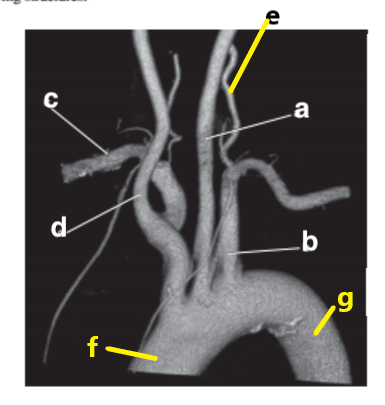

Left common carotid artery

Supplies blood to the left side of the neck and head.

Left subclavian artery

Supplies blood to the left upper extremity

Brachiocephalic trunk

Divides into the right common carotid and right subclavian arteries

Which letter is the Left common carotid ?

b

Left vertebral artery

Which letter is the left subclavian artery ?

Which letter is the Right common carotid artery ?

d

What is letter a ?

Which letter is the Right vertebral artery ?

f

c

Which letter is the right subclavian artery ?

g

a

Which letter is the brachiocephalic trunk ?